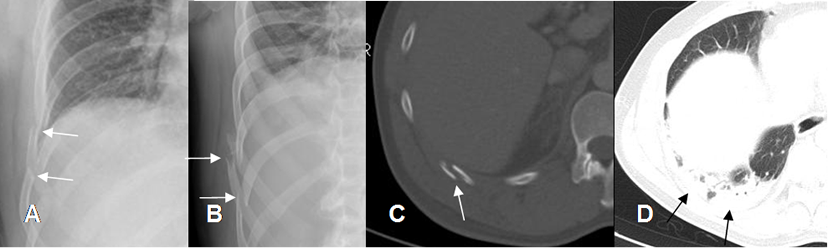

Fig 27 B. Contusión pulmonar.

A: Rx AP, B: Rx oblicua y C: TAC axial. Fracturas costales desplazadas en la base derecha.

D: TAC axial en ventana de pulmón. Zona de condensación en la base derecha, por contusión pulmonar.